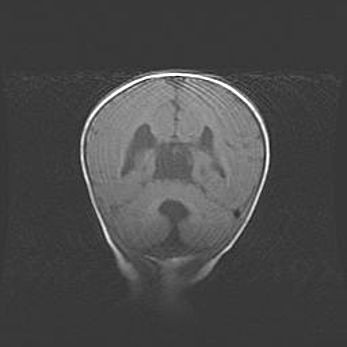

Аномалия Денди-Уокера. Признаки гипоплазии мозолистого тела.

Возраст: 5 месяцев 3 дня

Вес: 5550 г

Пол: мужской

Окружность головы: 39 см

Срок гестации: 40 недель

Аномалия Денди-Уокера – это порок развития головного мозга, для которого характерна триада симптомов: гипотрофия или аплазия червя мозжечка и/или полушарий мозжечка, расширение четвёртого желудочка с формированием ликворной кисты задней черепной ямки, гипертензионная гидроцефалия различной степени.

Гипоплазия мозолистого тела относится к дефектам внутриутробного этапа развития мозговой ткани, возникающим в процессе закладки структур головного мозга, что происходит на начальных этапах развития эмбриона.